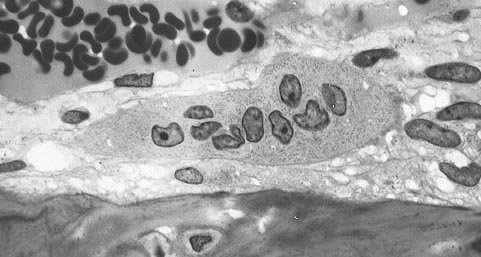

First of all, studies have found that obtain an osteoinducive effect we need to deliver supraphysiological doses, this means that we need to use huge amounts that are not normally present in our body, what can possibly go wrong? Well it turns out that the presence of high concentrations of BMP-2 causes the release of cytokines such as IL-6, IL-8 and TNF-alpha and the formation of seromas (Robin et al. 2010; Shahlaie and Kim 2008). As a consequence, there is an inflammatory response localized at the site where BMP-2 is injected (Zara et al. 2011). Our body does not react to biologics in a on/off fashion, often biologics evoke opposite responses. This a can be seen as a safety feature, so each response can be modulated if a biologic is released in disproportionate concentrations. That is also the case for BMP-2, so while it can enhance the osteogenic differentiation of stem cells it also increases the activity of cells that destroy bone, like the osteoclasts. BMP-2 does so by inducing osteoclastogenesis in vivo (Itoh et al. 2001) which results with more osteoclasts that actively destroy and remodel bone (James et al. 2016). Since BMP-2 also induces inflammation, we need to consider that in inflammatory environments osteoclasts show also increased activity, so we have more osteoclasts that also become much more active (Hori et al. 2006).